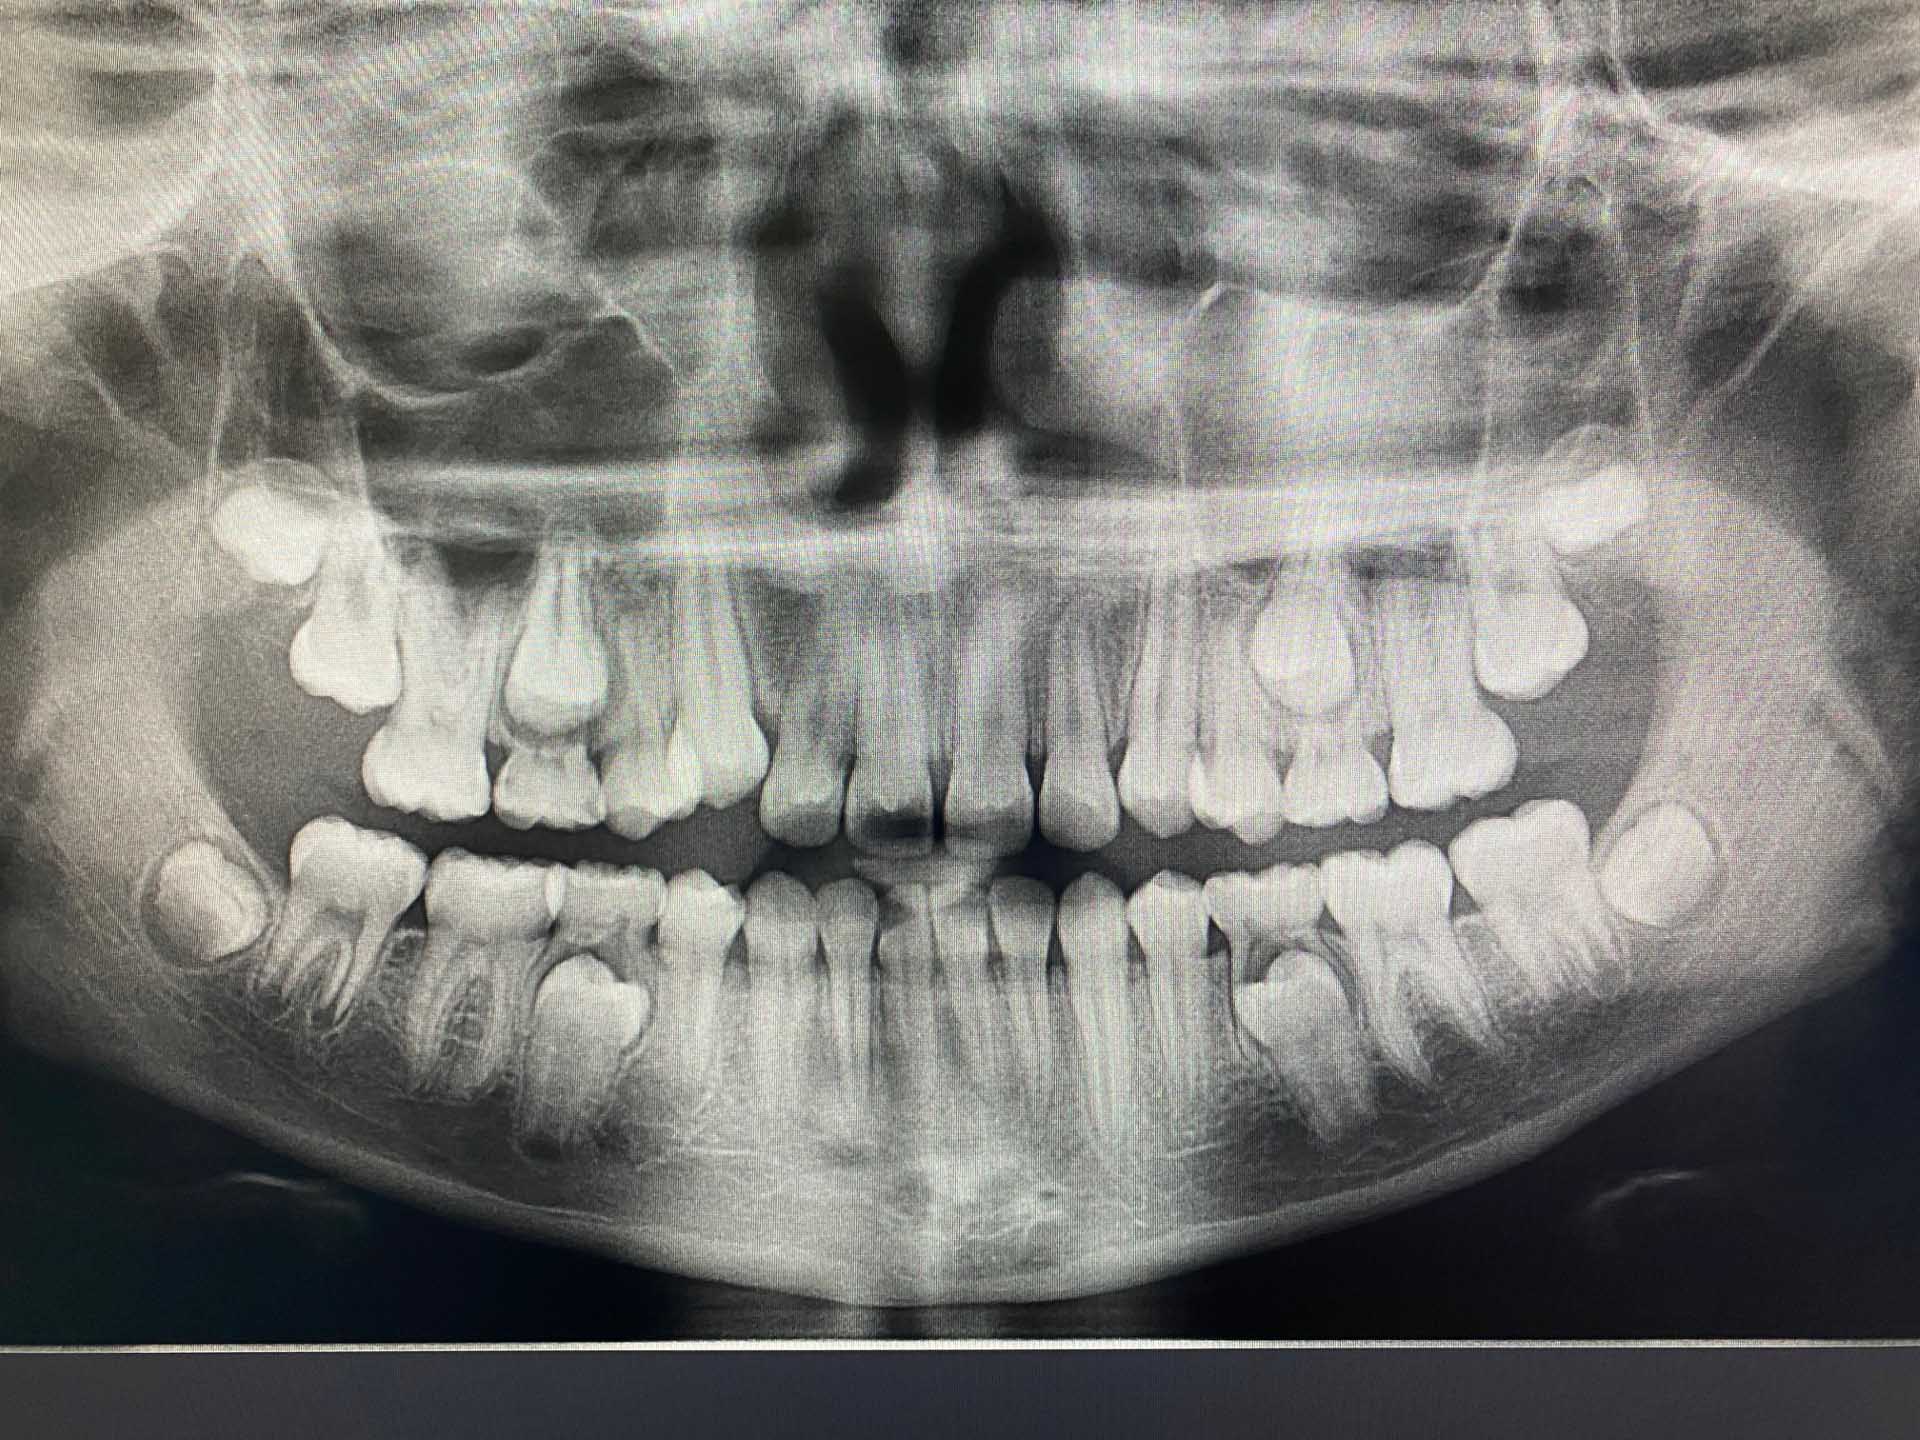

Oppstart med dokumentasjon

Vi tar nødvendige røntgenbilder, foto og kliniske modeller/skanninger. Dette danner det faglige grunnlaget for en individuell behandlingsplan og sikrer korrekt beregning av refusjon fra Helfo.

Foreldremøte etter ferdig behandling

Underveis i den aktive behandlingen tar vi kliniske bilder hver fjerde måned for å dokumentere fremdriften. Når reguleringen fjernes, kaller vi inn både pasient og foreldre til et foreldremøte ca. én måned etter fjerning av strengen. Her tar vi nye røntgenbilder og foto for å dokumentere sluttresultatet, og sammen med foreldre og barn går vi gjennom hvordan det så ut når vi startet og hvordan det ser ut nå.